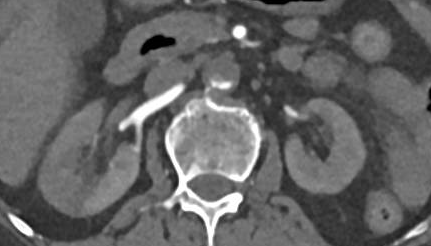

通过强化CT检查发现,患者腹主动脉肾动脉以远、左肾动脉及肠系膜下动脉开口处、双髂动脉及双侧下肢动脉血栓形成,右肾斑片状弱/无强化影,提示右肾梗死(图3-5)。

图3

图4

图5